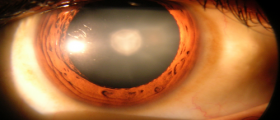

I am hoping some one will have some ideas to this problem. I started swimming in a masters program and I love it. But as the 1.5 hour session goes on, I notice that my vision starts to get a little blurry. By the time we are done, I am seeing double. :umno: After about an hour or so, it all clears up and I see fine. I wear contacts but they are in place the whole time. This only happens when swiming, I have never had problem like this any other time. Could it be the goggles?

I am hoping that maybe my astigmatism is aggravated by the goggles pushing my eyes apart. (sometimes certain sunglass give me a headache because of that.)